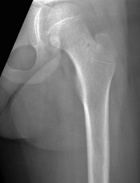

7 year old girl with five months of constant hip pain increasing in severity

Zoom image: Radiological image Radiological image.